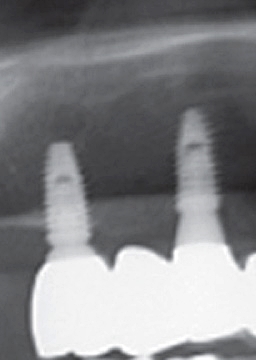

하지만 풀아치임플란트 시술은 기존 임플란트 치료와는 그 차이가 확연하게 나다 보니, 무치악 환자분들께서 선호하는 임플란트 시술이라고 하였어요. 이는 상악 하악에 각각 4개에서 6개까지만 임플란트를 식립하다 보니, 경제적인 측면에서 훨씬 부담이 덜할 수 있는 임플란트 시술이라고 하였어요. 이렇게 임플란트 시술을 한 후에 하나의 보철물을 이에 연결하다 보니 전체 치아의 저작기능이 회복할 수 있다고 하였어요.

풀아치임플란트 시술이란 상악 하악에 각각 4개에서 6개까지 인공 치근을 심어 잇몸뼈에 심은 후에 하나로 연결된 보철물을 임플란트에 고정하는 시술을 말하였어요. 이러한 풀아치 임플란트 치료는 발치부터 임플란트 시술, 보철물 장착까지 전 과정을 3D CT와 같은 디지털 시스템에 기반하다 보니 무절개 수술이 가능할 수 있었어요. 이러한 풀아치임플란트 시술은 기존 임플란트에 비하여 식립 개수가 절반 정도이다 보니 경제적인 부담이 줄어들 수 있었어요.

또한 뼈 이식 없이 남아 있는 건강한 잇몸 뼈를 이용하여 수술이 가능해지며, 이로 인하여 잃어버렸던 저작기능을 회복할 수 있기에 기능적인 측면에서도 큰 기대효과를 볼 수 있었어요. 게다가 인공치근 개수가 적다 보니 잇몸 절개로 인해 발생된 출혈을 줄일 수 있었으며, 수술 시간 및 회복 기간이 짧다 보니 전체적인 치료 기간이 일반 임플란트 치료에 비하여 짧을 수 있었어요.